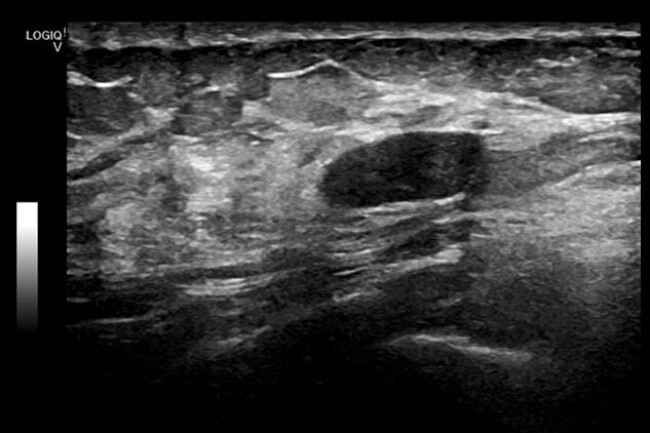

Infiltrazioni intrarticolari ecoguidate

con rilascio di referto ed immagini immediato